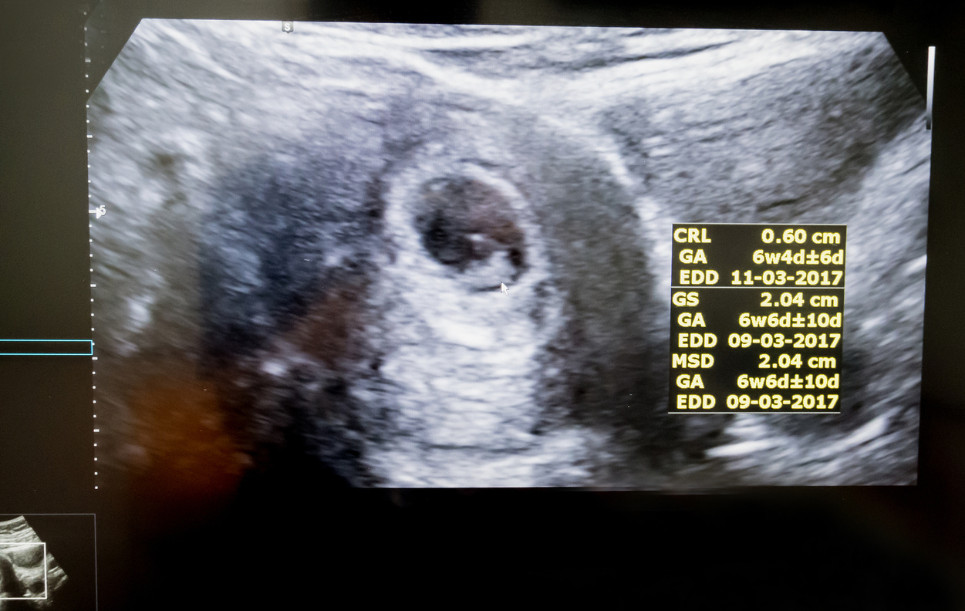

Alla fine della 4 settimana raggiungerà una lunghezza variabile tra i 2 e i 5 millimetri. Il suo cuore batte già, ma potrebbe non essere ancora visibile all’ecografia, che infatti viene rimandata ad almeno 8 settimane, e che più probabilmente mostrerà una camera gestazionale e il sacco vitellino, la placenta primordiale che nutre l’embrione attraverso un accenno di cordone ombelicale.